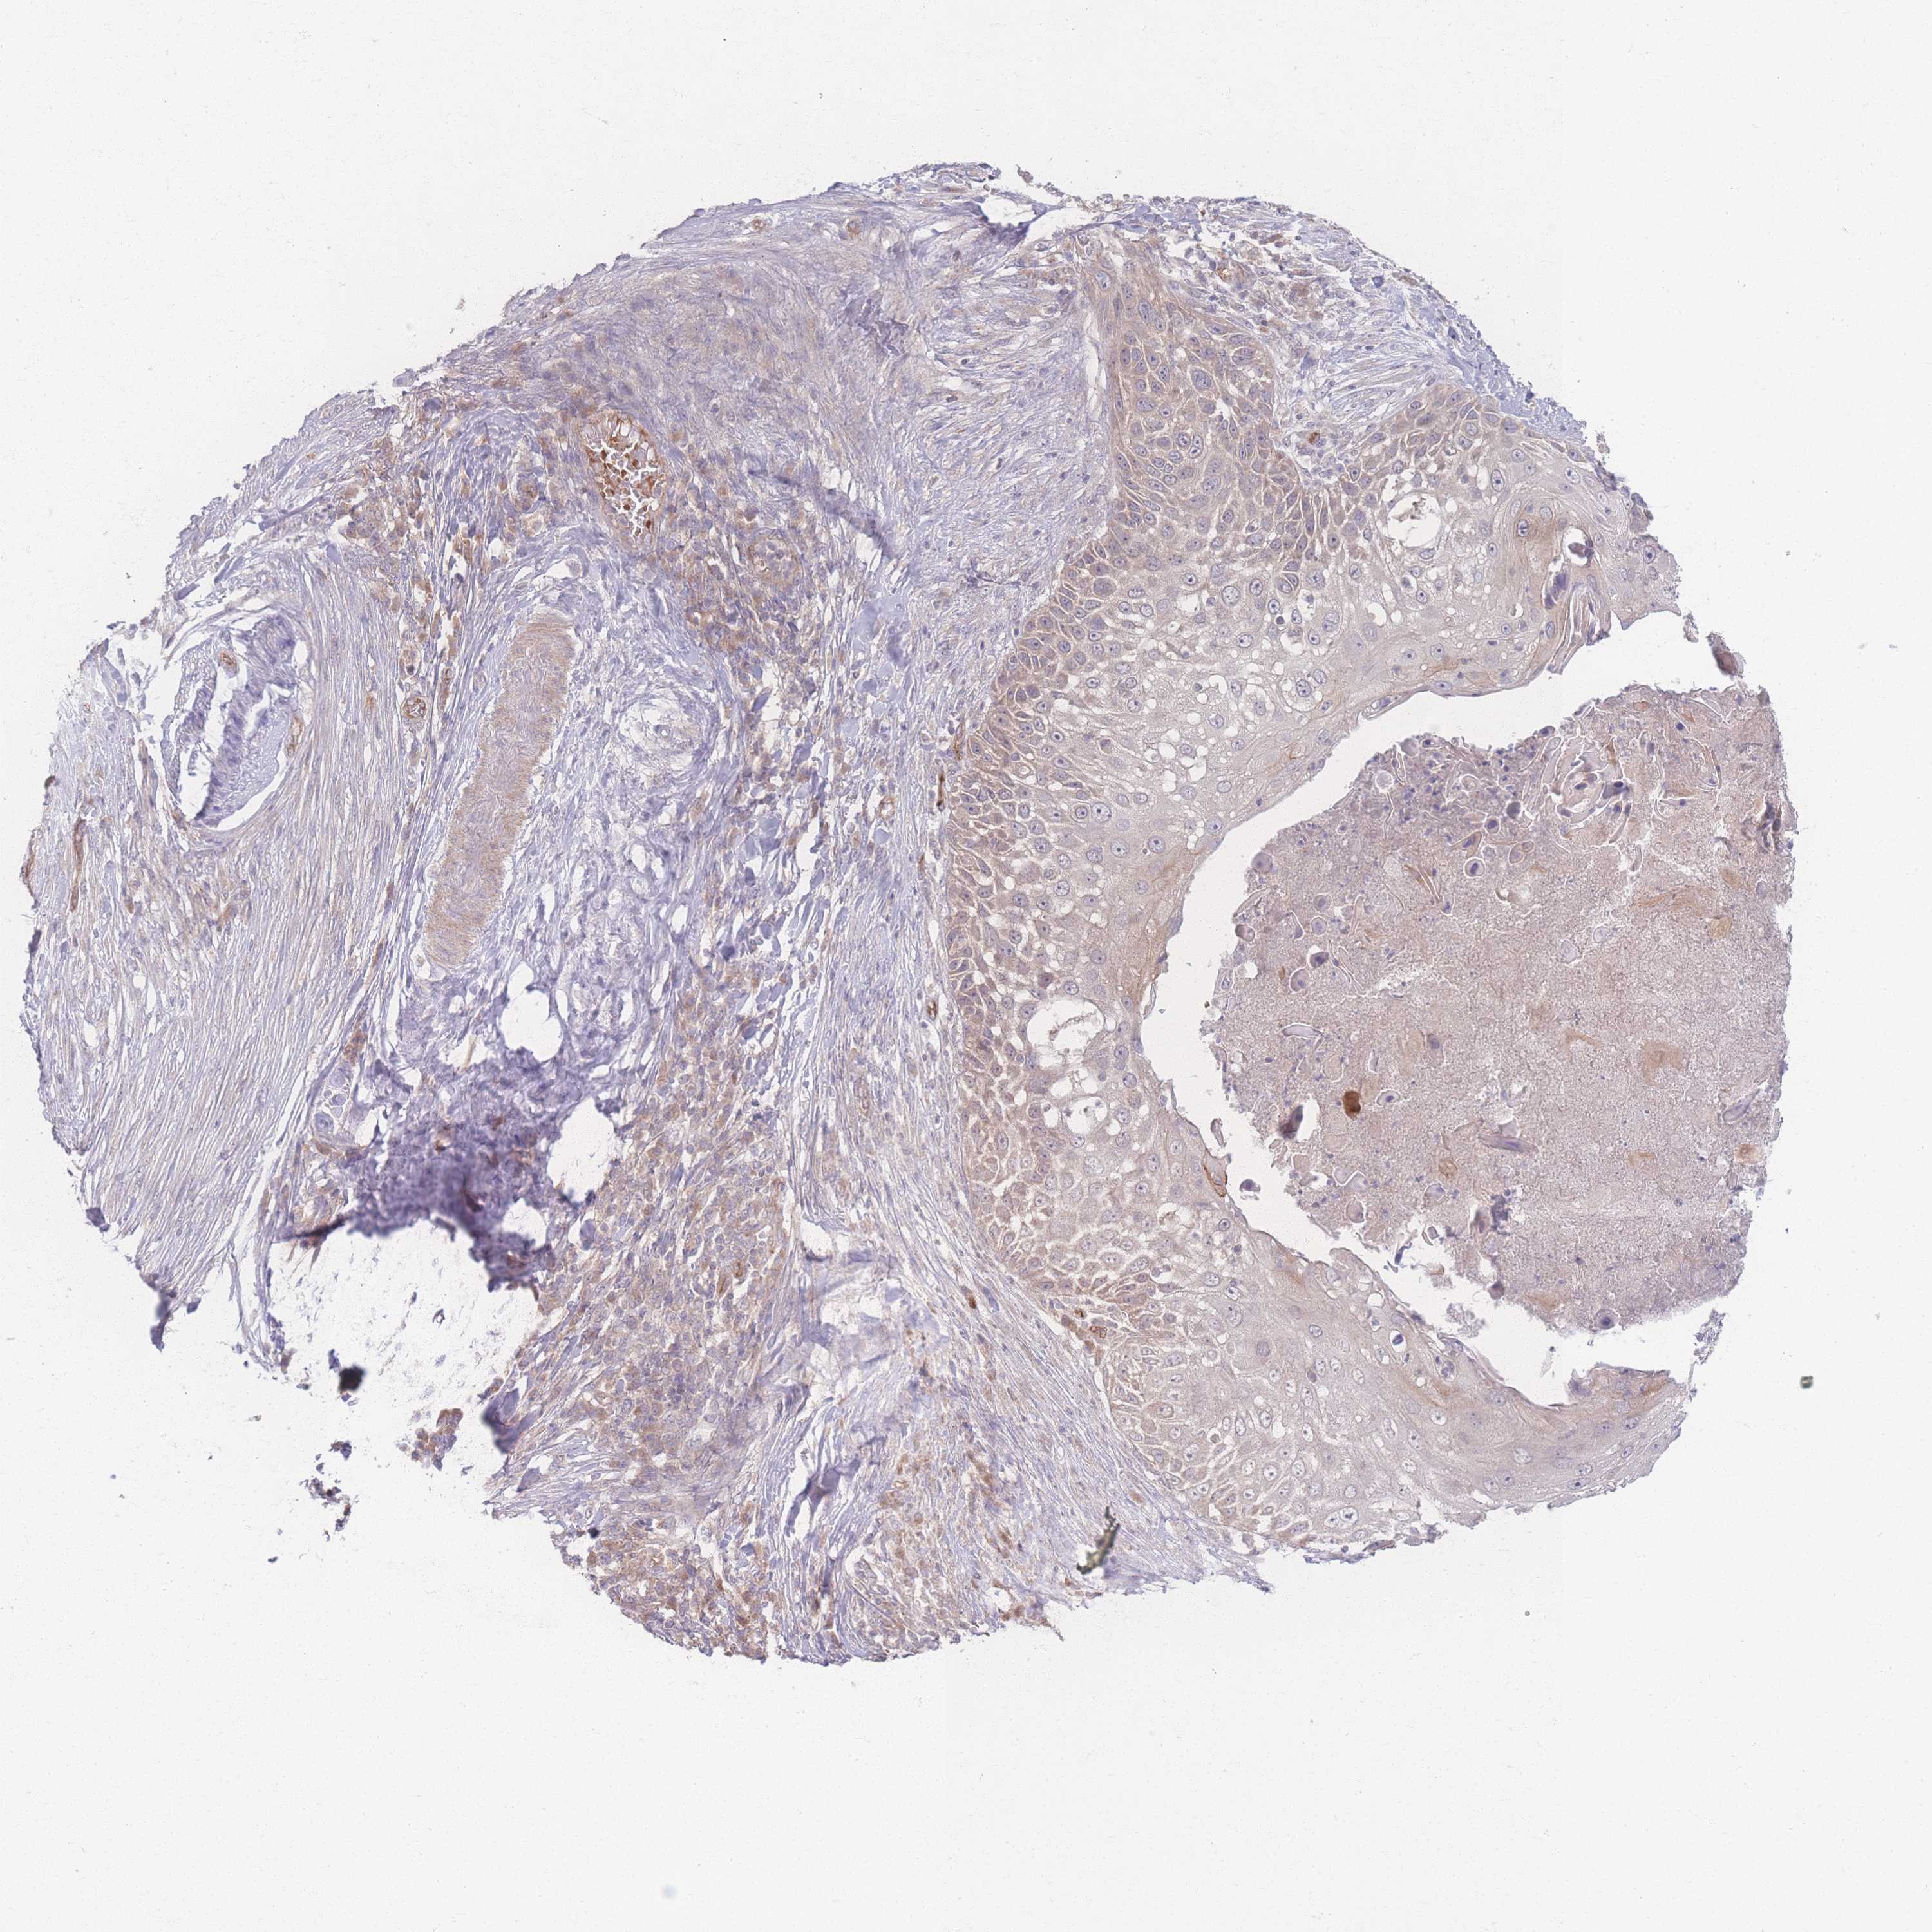

Basal cell and squamous cell cancer

SKIN CANCER - Protein expressioni

A mouse-over function shows sample information and annotation data. Click on an image to view it in a full screen mode. Samples can be filtered based on level of antibody staining by selecting one or several of the following categories: high, medium, low and not detected. The assay and annotation is described here.

Antibody stainingi

Antibody staining in the annotated cell types in the current human tissue is reported as not detected, low, medium, or high, based on conventional immunohistochemistry profiling in selected tissues. This score is based on the combination of the staining intensity and fraction of stained cells.

Each image is clickable and will lead to virtual microscopy that enables deeper exploration of all samples and also displays staining intensity scores, fraction scores and subcellular localization as well as patient and tissue information for each sample.

Antibody HPA036302

Staining

High

Medium

Low

Not detected

Intensity

Strong

Moderate

Weak

Negative

Quantity

>75%

75%-25%

<25%

None

Location

Nuclear

Cytoplasmic/membranous

Cytoplasmic/membranous,nuclear

Squamous cell carcinoma, NOS